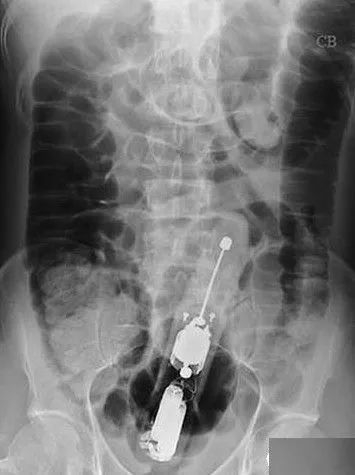

说到奇怪的患者,一定要说的是:

某些X光拍出来的东西也真是让人一言难尽

▼

不要问我这都是什么

我不知道